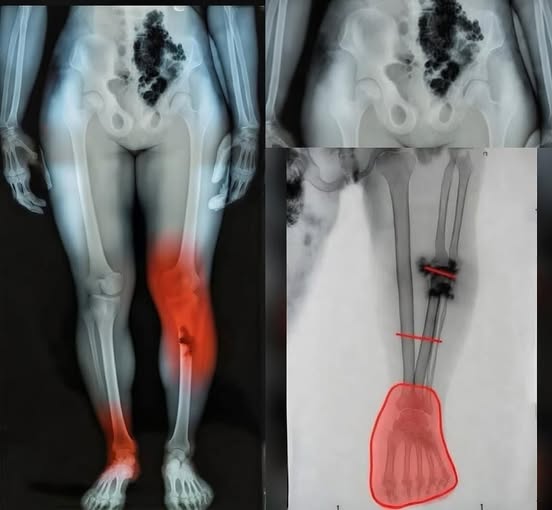

One of the most critical aspects of post-illness management is distinguishing between the expected slow pace of recovery and signs that require clinical intervention. While feeling tired is normal, certain “red flag” symptoms warrant an immediate conversation with your healthcare provider. New or unusual chest discomfort, significant shortness of breath during routine movements, or a persistent rapid heartbeat are indicators that the cardiovascular or pulmonary systems may need additional support. Similarly, unusual swelling in the lower extremities—legs, ankles, or feet—can signal a shift in fluid balance that is easily addressed when caught early. In 2026, healthcare providers emphasize that “waiting it out” is rarely the best strategy for these specific symptoms; early evaluation through simple diagnostic tools can prevent minor issues from escalating.